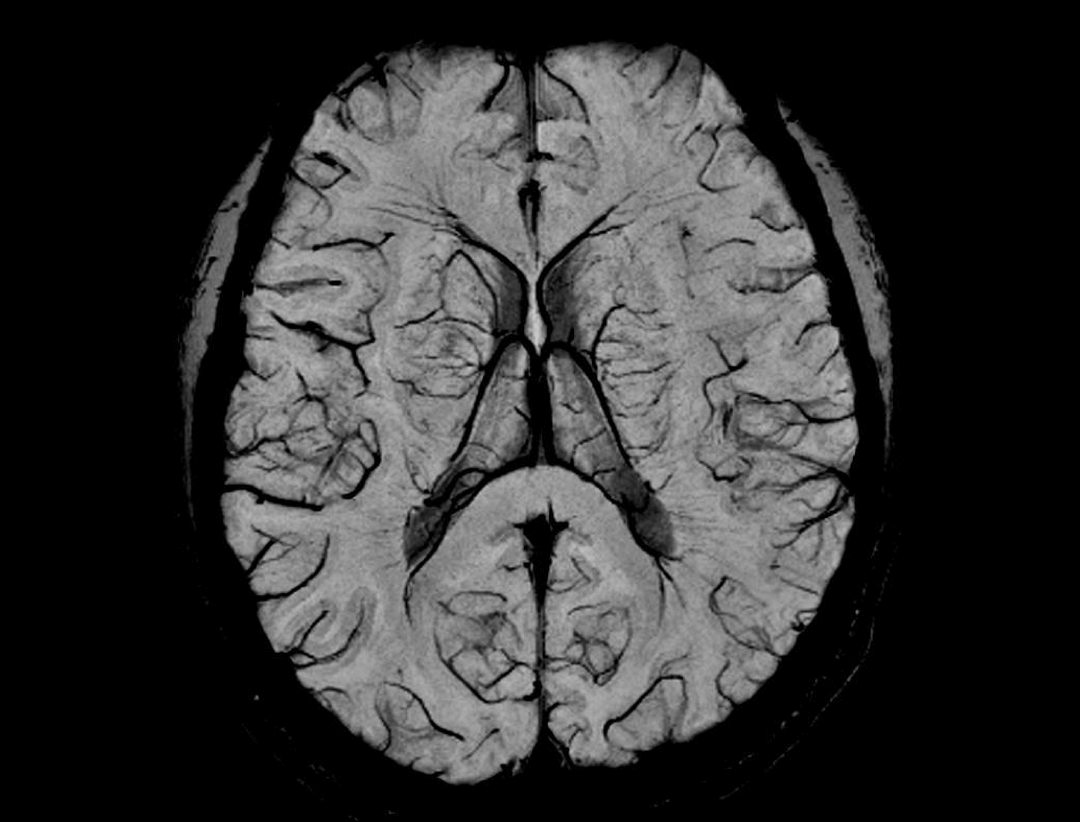

uMR® 770 provides high-speed imaging on all anatomy with significant scan time reduction.

Acceleration technology enables the uMR® 770 to significantly improve scan efficiency and increase patient throughput.